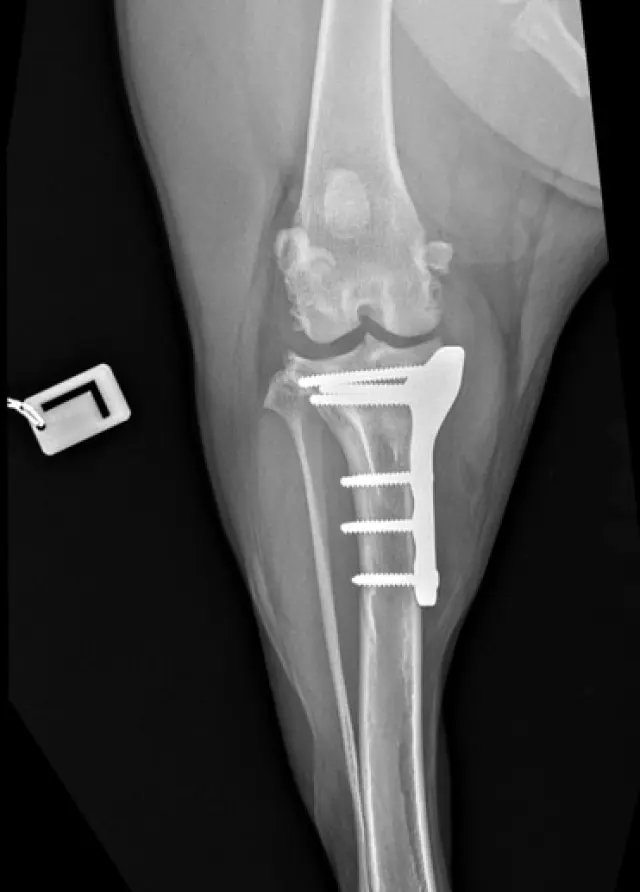

Veterinárna diagnostika odhalila dyspláziu bedrových kĺbov, chronické pretrhnutie väzov v oboch kolenách a pokročilú artrózu. Každý krok ju bolí, a hoci sa snaží byť veselá, vidno, že trpí.

Aby mohla opäť chodiť bez bolesti, potrebuje dve operácie kolien metódou TPLO. Prvá operácia je naplánovaná na ľavé koleno, druhá (po zahojení prvej) na pravé. Je to jej jediná šanca na návrat k normálnemu a dôstojnému životu.

Včera mala naša odvážna Lola prvú TPLO operáciu ľavého kolena.

Yesterday, our brave Lola had her first TPLO surgery on her left knee.

Ďalšia kontrola je v piatok a stehy jej odstránia 12. 09. Práve vtedy môžeme začať s fyzioterapiou. O 4 týždne pôjdeme na röntgen, a ak bude kosť dobre zhojená, môžeme pristúpiť k druhému kolenu.

Her next check-up is on Friday, and the stitches will come out on 12. 09. That’s when we can start her physiotherapy. In 4 weeks, she’ll have an X-ray, and if the bone has healed well, we can move on to the next knee.